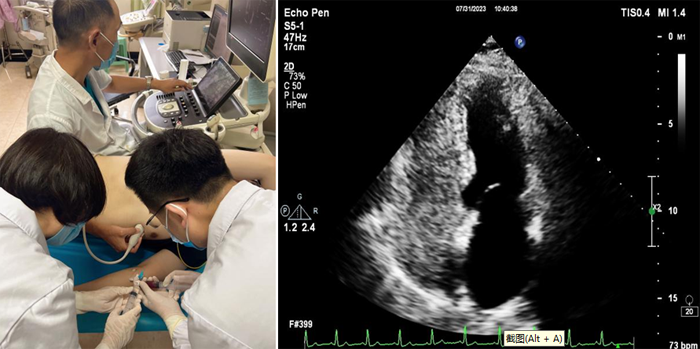

近日,我院超聲科聯(lián)合介入室、CCU 及神經(jīng)內(nèi)科成功完成首例經(jīng)胸右心聲學(xué)造影檢查。該項(xiàng)檢查填補(bǔ)了我院在超聲造影檢查的一項(xiàng)空白,該技術(shù)在魯西南地區(qū)屬領(lǐng)先水平,為我院心腦血管疾病的診斷又添新技術(shù)。

右心聲學(xué)造影又稱發(fā)泡實(shí)驗(yàn),是利用靜脈注射手震微氣泡生理鹽水造影劑,使右心系統(tǒng)顯影,造影劑氣泡直徑>10微米,平均約15微米,正常情形下微氣泡不能通過肺毛細(xì)血管網(wǎng),從靜脈血管輸入后只出現(xiàn)在右心,不進(jìn)入左心系統(tǒng)。由于微泡與血液存在明顯聲阻抗差,即使個(gè)別微泡(低速微量血流)也能清晰顯示,如果在患者的左心房或者左心室看到有微氣泡,則提示可能是從異常的通路由右心腔到達(dá)左心腔,即常說的右向左分流。同時(shí),檢查中還可以根據(jù)微氣泡在左心腔室出現(xiàn)的時(shí)間早晚,初步判斷異常是出現(xiàn)在心房心室間隔的缺損,還是出現(xiàn)在心外結(jié)構(gòu)的異常,例如肺動(dòng)靜脈瘺等。

6.右心造影劑制作:被檢者肘靜脈留置靜脈通路。連接三通管,使用一支20ml注射器抽取8ml生理鹽水后再回抽1ml受檢者自體血液,連接三通管的一端;再用一支20ml注射器抽取1ml空氣連接三通管的另一端;然后將兩支注射器通過三通管快速互相推送震蕩20次,使空氣、生理鹽水、血液三者均勻混合。

7.操作時(shí),造影劑以彈丸方式快速注入。留存動(dòng)態(tài)圖,靜息狀態(tài)操作1次,Valsalva動(dòng)作后操作 1次至2次。

8.選取四腔心切面,分別觀察靜息狀態(tài)及Valsalva動(dòng)作后左心腔內(nèi)微泡顯影情況。